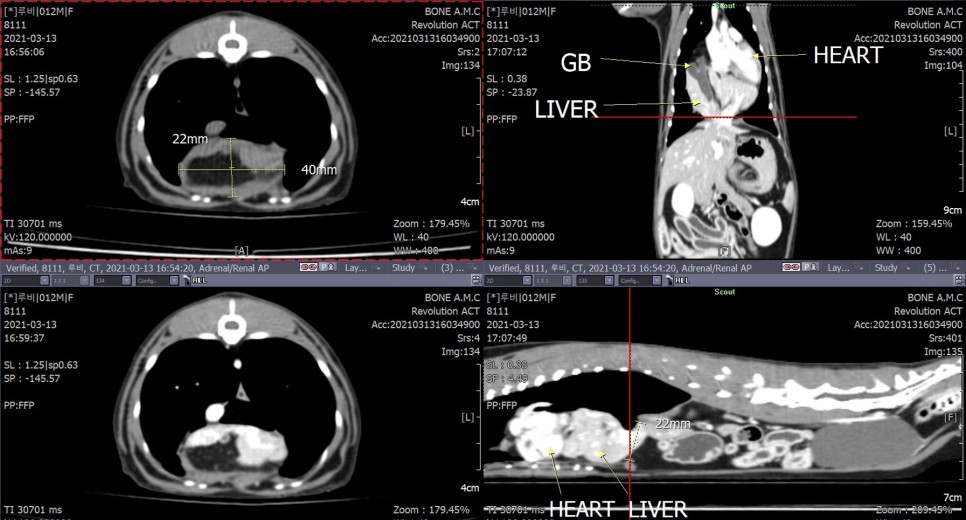

CT 검사로 횡격막 결손부의 크기와 심낭 내에 변위된 복강 장기의 위치를 정확하게 조사했습니다.

또한 선형 이물질에 의해 구불구불한 장분절이 광범위하게 확인되었습니다.